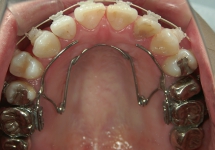

バイヘリックス(BH)

QHと同じく顎の骨幅を広げる効果があり、歯列の幅が広がります。ヘリカルループというワイヤーのくるくるが2つのため、QHよりも力は弱いですが、舌がある下顎には、かさばらないBHを使用します。